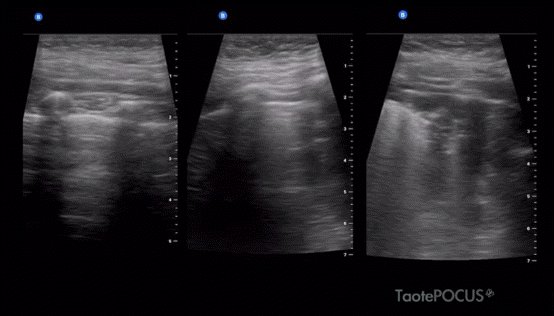

โž– Probe on right axilla (Long & trans)

ใ€ฝ๏ธBacterial Pneumonia

A profile Alveolar Consolidation

(Normal) + Air Bronchogram